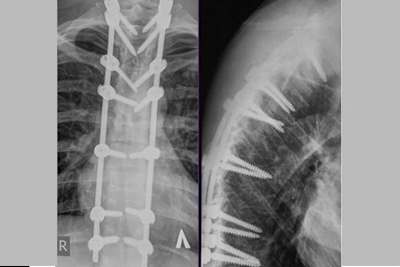

Alexandr Tonkov: 14 Schrauben in der Wirbelsäule

Nach seinem verheerenden Crash auf der Halbinsel Kamtschatka Anfang September wurde Alexandr Tonkov in die 6000 km entfernte russische Hauptstadt Moskau ausgeflogen, wo mehrere gebrochene Wirbel mit Titanstäben stabilisiert und verschraubt wurden. Mindestens 14 Schrauben sind auf dem Röntgenbild zu erkennen, das Tonkov in den sozialen Medien veröffentlichte.